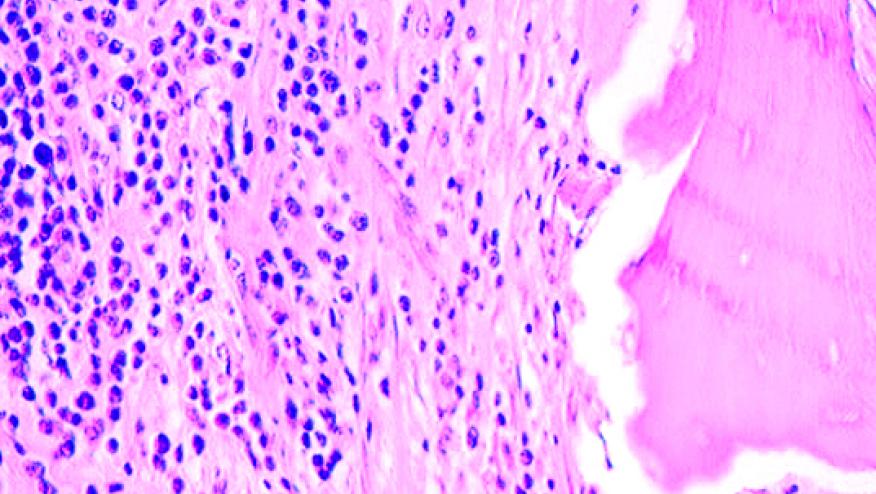

A Mayo Clinic analysis of trends in osteomyelitis disclosed 760 new cases between 1969 and 2009 in Olmstead county. Rates increased from 11.4 cases per 100,000 person-years for the period from 1969 to 1979 to 24.4 per 100,000 person-years in the period from 2000 to 2009. Rates were stable in children but tripled in those over age 60 years, especially amongst diabetics. Forty percent were due to Staphylococcal infection. The reasons for the increase in osteomyelitis between 1969 and 2009 are unclear but could comprise a variety of factors, including changes in diagnosing patterns or increases in the prevalence of risk factors (e.g., diabetes) in this population.